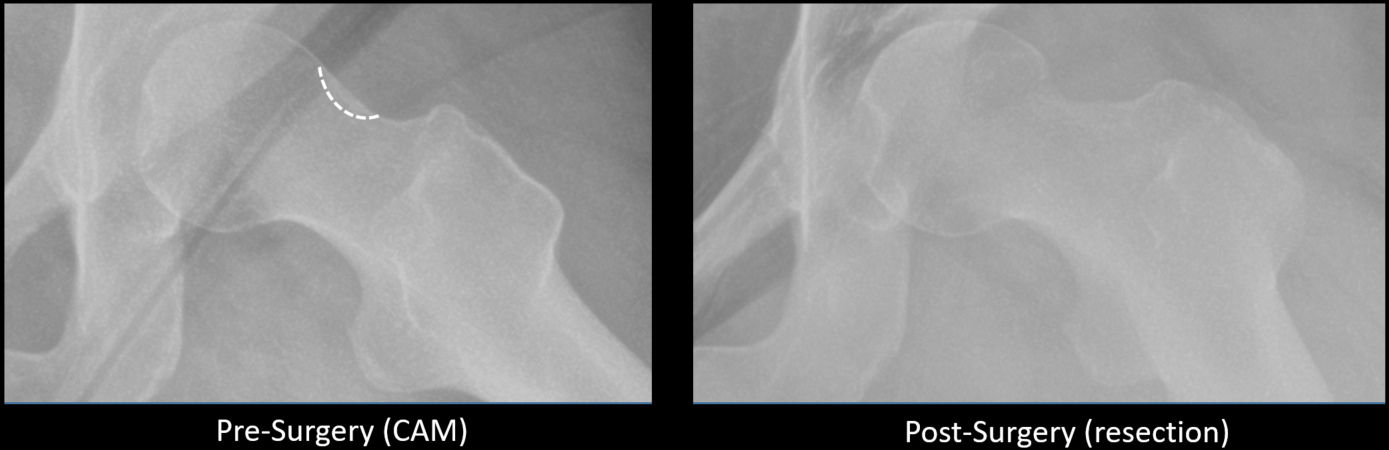

He ended up seeing five orthopedic surgeons, but it wasn’t until he was referred to Jarvis that things started to make sense. Jarvis ordered a special lateral x-ray, which revealed the easy-to-overlook FAI.

Jarvis explained that the hip is a ball-and-socket joint. In Johnson’s case, an irregular bone growth known as a CAM prominence developed on the femoral head (top of thigh bone) causing pain to occur when it rotated (as the ball) into the acetabulum (hip socket). Over time, this grinding caused a tear to develop in the labrum – the protective layer of cartilage between the two joints.

Jarvis recommended a minimally invasive two-step outpatient hip arthroscopy procedure. Through tiny pin-hole incisions, he would insert a camera and a high-speed burring tool to smooth over the CAM bone growth, thus removing the impingement and allowing the femoral head to rotate freely. Then, he would repair and reattach the torn labrum to the bone. Johnson agreed to the surgery but admitted that he still felt nervous.